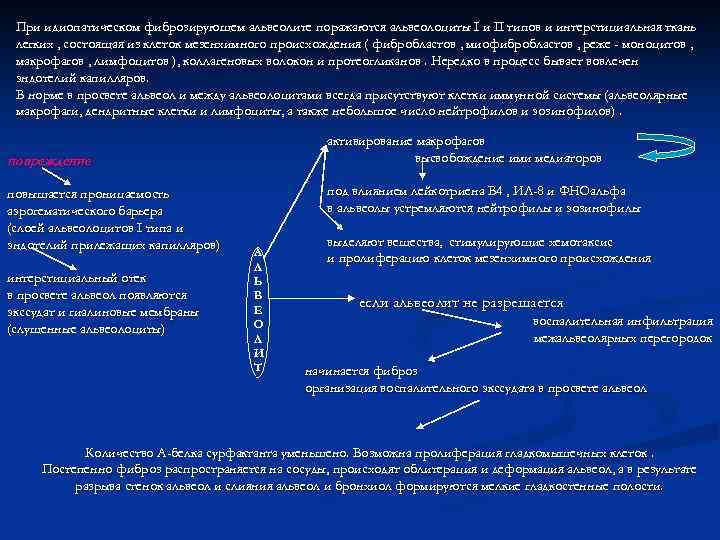

При идиопатическом фиброзирующем альвеолите поражаются альвеолоциты I и II типов и интерстициальная ткань легких , состоящая из клеток мезенхимного происхождения ( фибробластов , миофибробластов , реже - моноцитов , макрофагов , лимфоцитов ), коллагеновых волокон и протеогликанов. Нередко в процесс бывает вовлечен эндотелий капилляров. В норме в просвете альвеол и между альвеолоцитами всегда присутствуют клетки иммунной системы (альвеолярные макрофаги, дендритные клетки и лимфоциты, а также небольшое число нейтрофилов и эозинофилов). активирование макрофагов высвобождение ими медиаторов повреждение повышается проницаемость аэрогематического барьера (слоей альвеолоцитов I типа и эндотелий прилежащих капилляров) интерстициальный отек в просвете альвеол появляются экссудат и гиалиновые мембраны (слущенные альвеолоциты) под влиянием лейкотриена В 4 , ИЛ-8 и ФНОальфа в альвеолы устремляются нейтрофилы и эозинофилы А Л Ь В Е О Л И Т выделяют вещества, стимулирующие хемотаксис и пролиферацию клеток мезенхимного происхождения если альвеолит не разрешается воспалительная инфильтрация межальвеолярных перегородок начинается фиброз организация воспалительного экссудата в просвете альвеол Количество A-белка сурфактанта уменьшено. Возможна пролиферация гладкомышечных клеток. Постепенно фиброз распространяется на сосуды, происходят облитерация и деформация альвеол, а в результате разрыва стенок альвеол и слияния альвеол и бронхиол формируются мелкие гладкостенные полости.